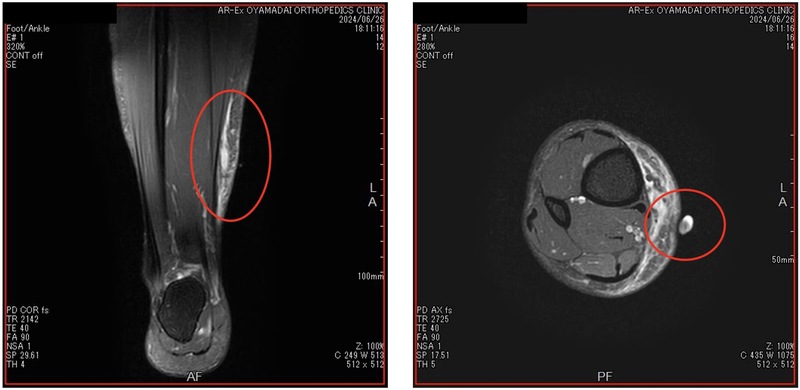

サッカー選手の下腿膿瘍

競技:サッカー

受傷原因:プレー中相手スパイクのポイントが刺さり受傷

画像診断 : 右下腿内側血腫組織化(+)